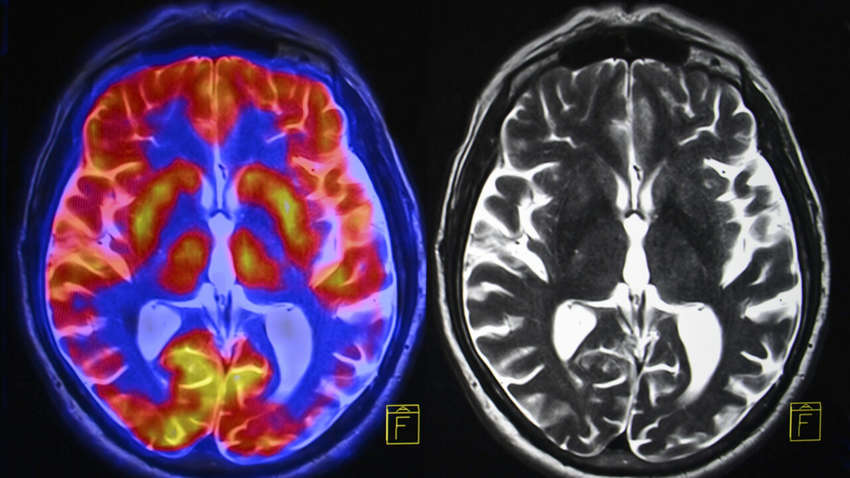

Здесь на помощь приходит новое приложение, разработанное Кардиффским университетом и Национальной академией программного обеспечения. Используя реальные изображения мозга пациентов с болезнью Альцгеймера, приложение обучает добровольцев распознавать правильную форму свода на отсканированном изображении.